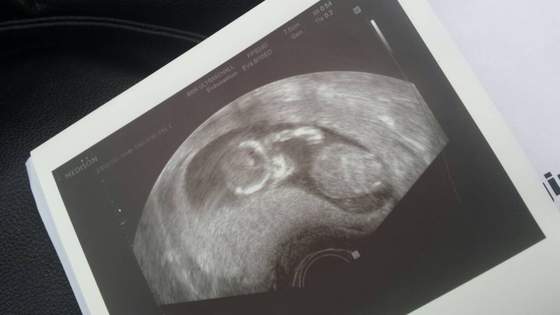

ja tak samo podchodzeIwo jesli lekarz mi nie pawie wyraznie ze mam zrobic PAPPA to nie bede robic. Chce uniknac stresu bo tak naprawde nic sie nie zmieni. Staram sie byc dobrej mysli!

pappa tylko daje prawdopodobienstwo a nie pewnosc takze jezeli NT bedzie u nas dobre (a beedzie ) to nie robie badan prenatalnych mimo wieku